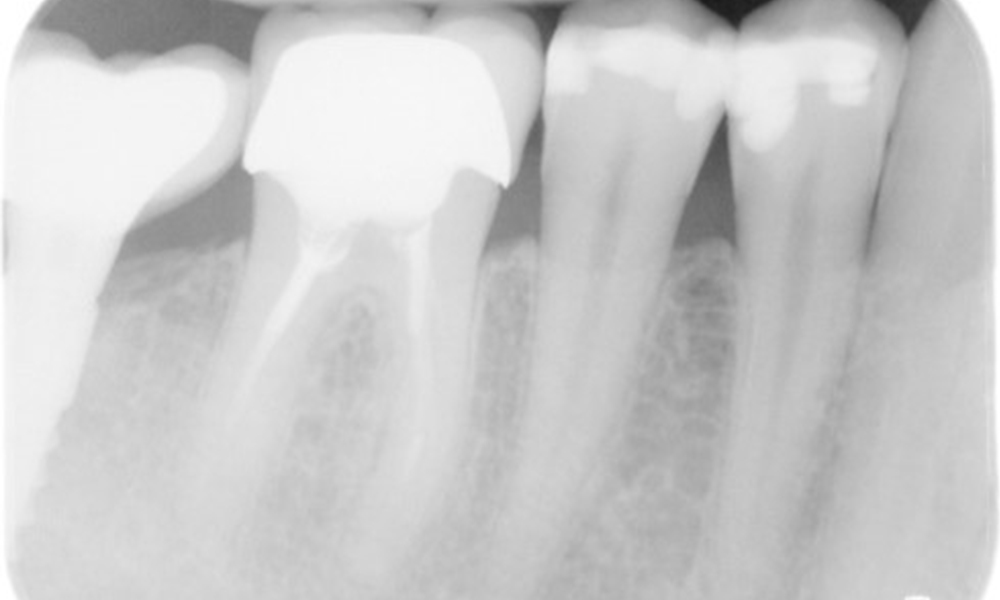

X-ray images (or bitewing X-rays)

X-ray images (or bitewing X-rays) taken on: 18/02/2021

The X-ray image shows the bone loss

The X-ray images show the bone loss.